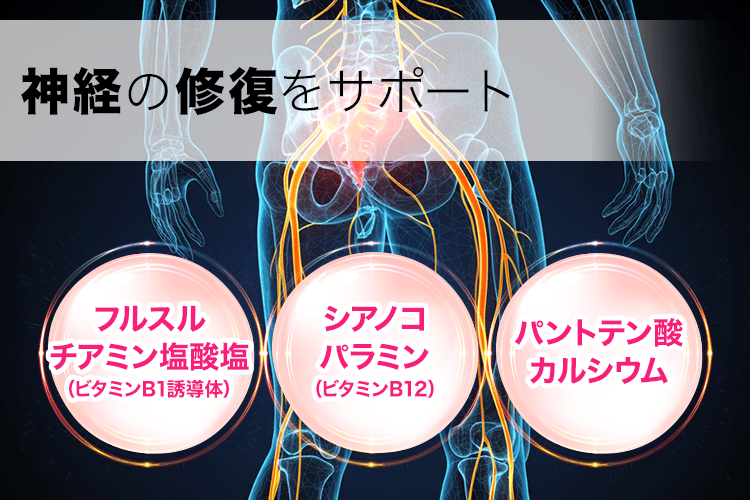

しかも残念なことに、

神経は一度損傷すると

自力で修復するのはほぼ不可能…

だから、

放置してても治ることはなく、

悪化すると寝たきりになる危険も😱

だから坐骨神経痛を根本解決するには

内側から神経を修復するしかないんです。

そして最後に

神経の修復に関わる3つの成分↓

※効果には個人差があります

この3つの成分が、

梨状筋によって損傷した坐骨神経を

修復してくれるんです!